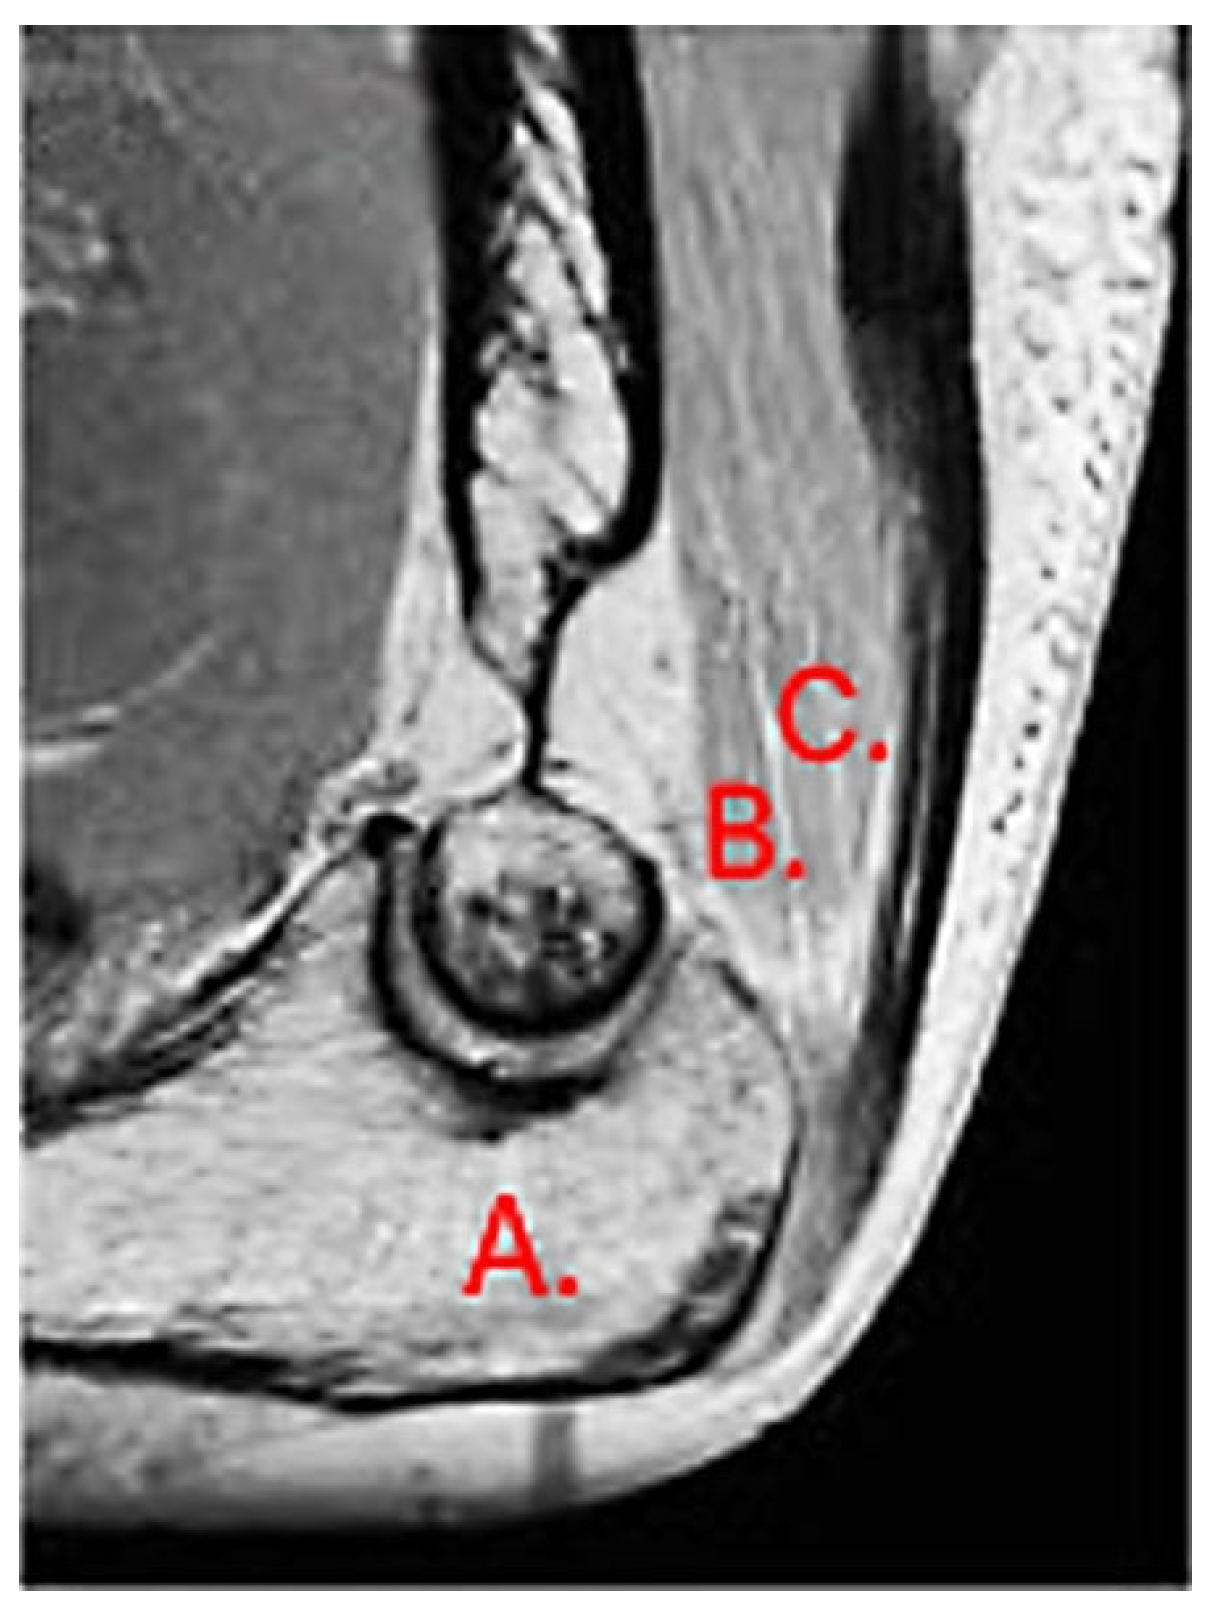

The most common tendon injuries are rotator cuff tears of the shoulder, hand flexor injuries, and achilles tendon injuries [1]. Triceps tendon rupture is the least reported among all the tendon injuries in the literature [2,3]. 65 years ago, Anzel evaluated a series of 1014 patients with tendon ruptures in various locations, and triceps tendon ruptures accounted for only 0.8% of this series [4]. Currently the prevalence is increasing, and the prevalence of triceps tendon injuries has been found to be 3.8% [5]. Theoretically, the types of tendon injuries are tendon avulsion or inside the muscle belly. In practice, a rupture almost always occurs in the area of the tendon-bone junction, and the cause is an eccentric contraction of the triceps causing a tendon deformity of more than 8% [6]. Traditionally the triceps tendon has a uniform attachment to the olecranon ulnae. This premise has caused problems in assessing the degree of damage in traumatic triceps tendon ruptures. In 2006, an anatomic study by Madsen confirmed that in most cases the medial head of the triceps has a single attachment to the olecranon ulnae [7]. This insertion is located in a deeper layer and forms a narrower part of the attachment, and very rarely is only this part damaged [8]. The long and lateral head of the triceps has a common attachment that runs more superficially, gradually extending laterally into the surrounding area towards the musculus anconeus, which helps to strengthen the bone-tendon junction. The width of the attachment correlates with the size of the olecranon and ranges from 20 to 40 mm. Paradoxically, the thickness of the tendon is not as pronounced. The attachment itself occupies a large surface area, reaching 400 mm2 in diameter and is dome-shaped [9]. These current findings are particularly important in partial tendon ruptures when a decision has to be made whether to proceed conservatively or with surgical revision. MRI is an appropriate method of choice to accurately assess the current condition. A schematic representation of the three basic types of partial DTTR rupture can be seen in Figure 1, while the normal anatomic attachment relationships of the triceps tendon in sagittal section to the olecranon ulna and a sub-complete rupture of the triceps tendon of the right hand are shown in Figure 2 and Figure 3. Furthermore, the place of attachment of the individual heads of the triceps to the olecranon ulnae is presented in Figure 4.

Figure 2. Normal anatomic attachment relationships of the triceps tendon in sagittal section to the olecranon ulnae. MRI: A—olecranon, B—medial head, C—common tendon of lateral and long head (own source).